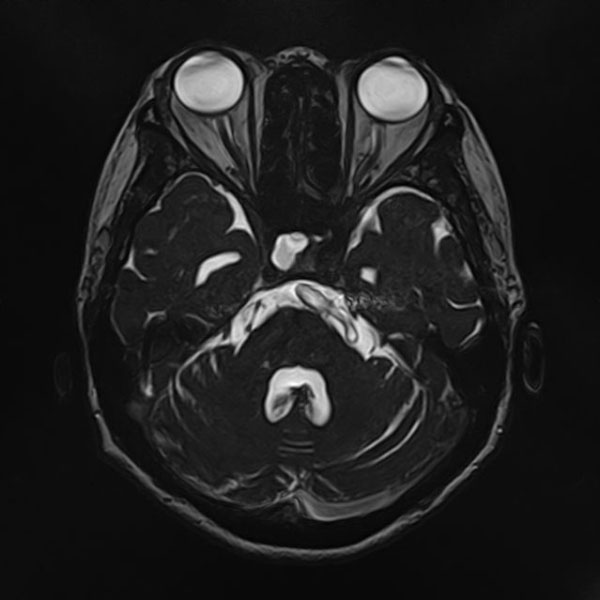

手術前

(MR1)